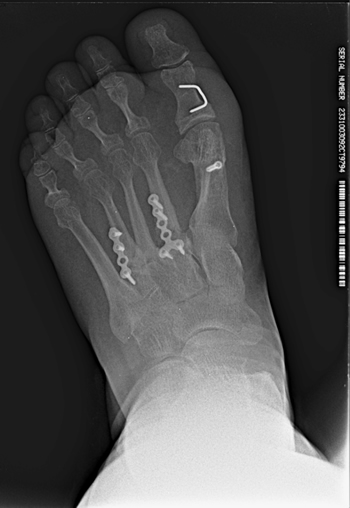

Con fecha 16 de junio de 2015 se realizó la intervención quirúrgica bajo sedación consciente y con anestesia raquídea. Se usaron 2 g de cefazolina intravenosa como profilaxis antibiótica previamente al inflado del torniquete colocado en el tobillo a una presión de 230 mm Hg. Se realizaron cuatro incisiones: una incisión medial para la corrección del hallux abductus valgus, una incisión dorsal sobre segundo metatarsiano, otra incisión dorsal sobre cuarto metatarsiano, y una cuarta incisión en la zona posterior lateral del calcáneo derecho para la obtención del autoinjerto. A través de la primera incisión, se realizó la corrección del hallux valgus con liberación de la contractura lateral vía intrarticular, liberando el ligamento suspensorio y con tenotomías de la cabeza lateral del flexor corto del hallux y del abductor del hallux, junto con osteotomía de Scarf en el primer metatarsiano fijado con un tornillo tipo Herbert (3.0 mm META SCREW® con rosca larga de 20 mm) (Debramedix; Almoradi, Alicante, España) y osteotomía de Akin en la falange proximal (fijado con grapa medial). A través de la segunda incisión en el segundo metatarsiano, se realizó desbridamiento y limpieza de la zona de la pseudoartrosis (Figura 3A). Se midió la longitud del defecto óseo, que era 7 mm, y se obtuvo el autoinjerto de calcáneo del pie derecho (Figuras 4A y 4B) para luego implantarlo en el metatarsiano (Figura 3B). El defecto de calcáneo fue rellenado con sustituto óseo sintético, una cerámica sintética de hidroxiapatita 65 % y fosfato tricálcico 35 % (CERAFORM®, Tecknimed; L’union, France). El autoinjerto de calcáneo utilizado es principalmente de hueso esponjoso y presenta hueso cortical obtenido de las paredes dorsal y lateral del calcáneo, de manera que se situó la porción del injerto con cortical en posición dorsal para resistir mejor las fuerzas de compresión a la carga. Se estabilizó con placa de bloqueo en “T” (miniplaca en T 2/4 orificios 30 x 5 mm con tornillo bloqueado de 2.0 mm) (Debramedix; Almoradi, Alicante, España)(Imagen 8). A través de la tercera incisión se realizó una estabilización del cuarto metatarsiano con placa recta dorsal (miniplaca recta 5 orificios 29 x 5 mm con tornillos bloqueados de 2.0 (Debramedix; Almoradi, Alicante, España). Se realizó finalmente un bloqueo postoperatorio local con 8 ml de bupivacaína 0.5 % junto con 2 cc de betametasona (Celestone®Cronodose®, Schering-Plough; New Jersey, USA). La Figura 5 muestra la radiografía postoperatoria.

Figura 5. Imagen postoperatoria tras la cirugía.